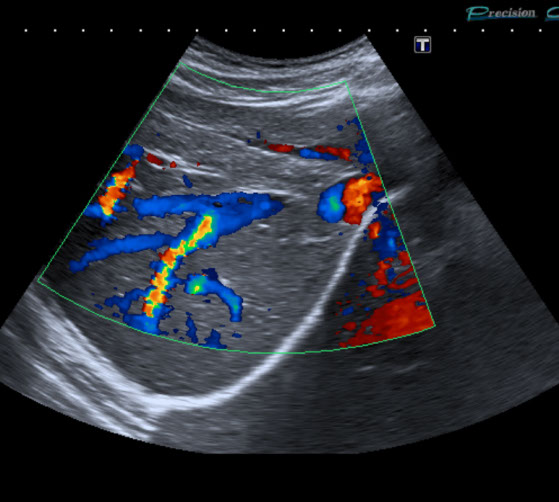

• Die großen Bauchgefäße (speziell Bauchschlagader) zur Erfassung von Gefäßaussackungen (Aneurysmen) oder Engstellen (Stenosen) sowie bei Verschlüssen, Thrombosen der Pfortader und anderer Bauch- und Beckengefäße.